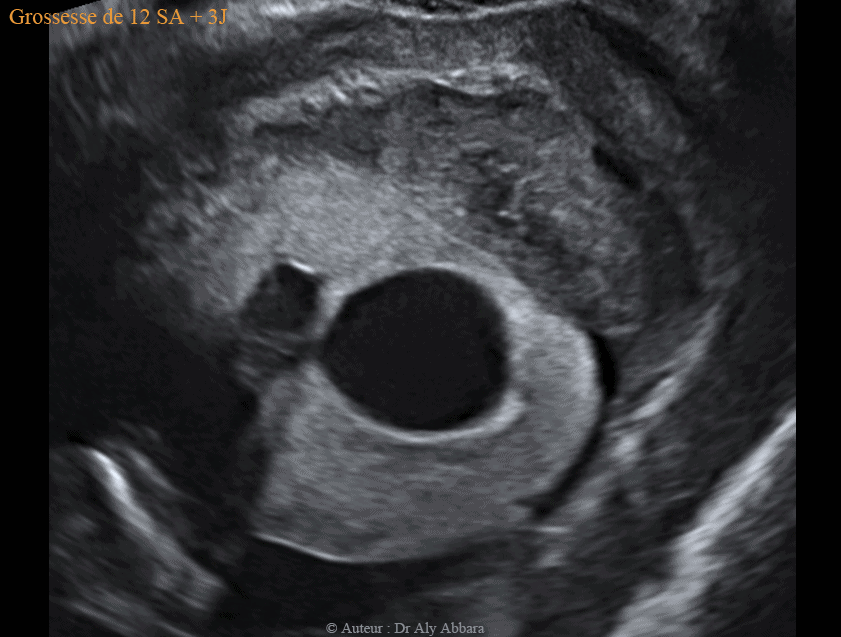

Kyste placentaire cytotrophoblastique intra-parenchymateux associé à la présence d'un hématome rétroplacentaire - grossesse de 12 SA et 3 J

Dans le cas présenté dans cet article, le kyste placentaire intra-parenchymateux, cytotrophoblastique, prend la forme d'une formation intra-placentaire, unique, uniloculaire, à contenu anéchogène et à paroi hyper-échogène, mais sans végétations endophytiques et sans zone d'épaississement.

Ce kyste évolue dans le parenchyme placentaire, mais au niveau d'un de ses deux pôles, il atteint la face fœtale du placenta à un point correspondant à la zone de l'insertion du cordon ombilical.

Le kyste mesure 26 x 21 x 23 mm de diamètre (6,4 cm3 de volume).

Il a été mis en évidence à 12 SA et 3 jours ; il est en association avec un décollement partiel du placenta aboutissant à la formation d'un hématome rétro-placentaire (et rétro-cervical utérin) de 42 x 21 x 52 mm de diamètre (soit 24 cm3 de volume).

Cet HRP se manifeste cliniquement par des métrorragies modérées depuis plusieurs semaines, mais la grossesse évolue normalement : foetus vivant et morphologiquement normal, avec longueur crânio-caudale "LCC" = 61,75 mm, et clarté nucale = 1,51 mm.